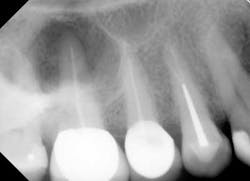

1. Not all teeth should be treated the same. Anatomy dictates technique. Having only one clinical instrumentation or obturation technique is not adequate when the tooth dictates a different method than the one generally employed. For example, if the clinician only has standard K files (Mani K files) and the canal is calcified, having the option of employing a hand K file designed for such calcification (Mani D finders) allows more efficient negotiation of calcification. Having only one hand file option or using the wrong hand file can lead to iatrogenic outcomes (blocked, ledged canals among other issues). See Figs. 1-2. Similarly, using a crown-down approach to instrumentation may risk iatrogenic outcomes when a step-back approach is more appropriate.